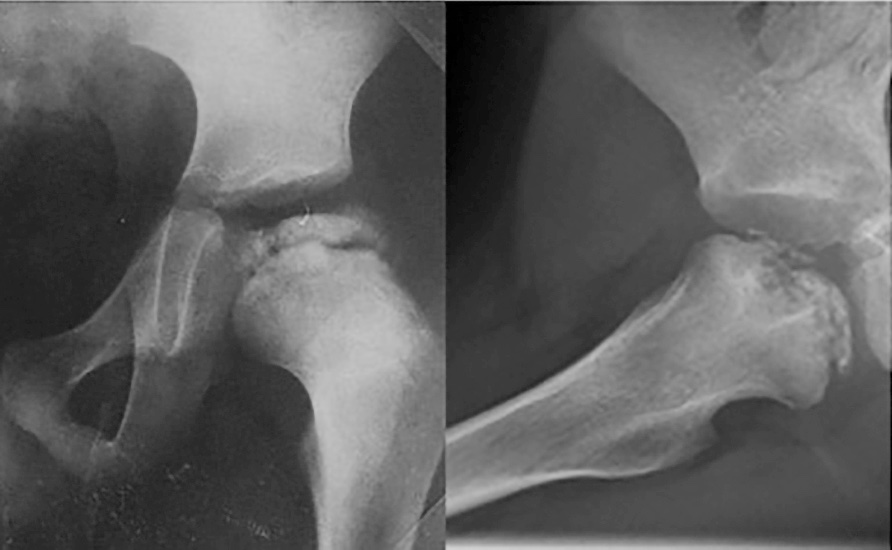

Le proiezioni da eseguire in caso di sospetto sono l’anteroposteriore e la frog-lateral d’anca (Fig. 1). In base alle manifestazioni radiografiche è possibile classificare la malattia sulla base dell’estensione e della gravità e distinguere due fasi: attiva, quando l’epifisi femorale appare sclerotica con o senza presenza di collasso e fenomeni di riossificazione, di guarigione, quando nessun residuo osseo avascolare può essere radiologicamente identificato 5.